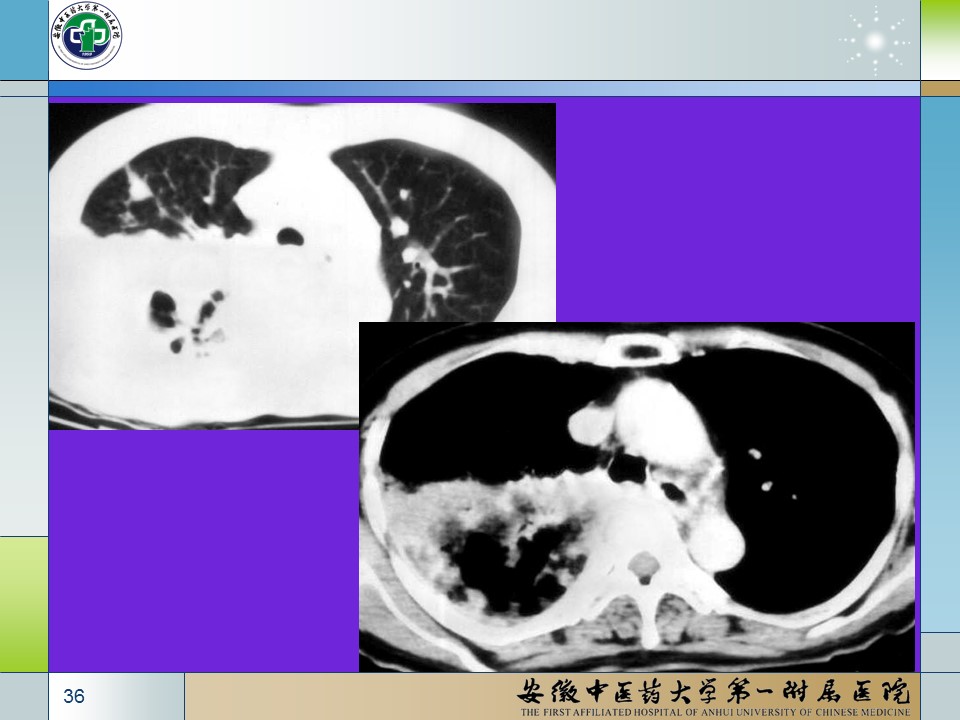

【PPT】肺部感染性疾病的CT表现分析